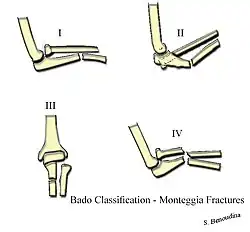

There are four types (depending upon displacement of the radial head):[3]

- I - Extension type (60%) - ulna shaft angulates anteriorly (extends) and radial head dislocates anteriorly.

- II - Flexion type (15%) - ulna shaft angulates posteriorly (flexes) and radial head dislocates posteriorly.

- III - Lateral type (20%) - ulna shaft angulates laterally (bent to outside) and radial head dislocates to the side.

- IV - Combined type (5%) - ulna shaft and radial shaft are both fractured and radial head is dislocated, typically anteriorly.

These are known as the Bado types.